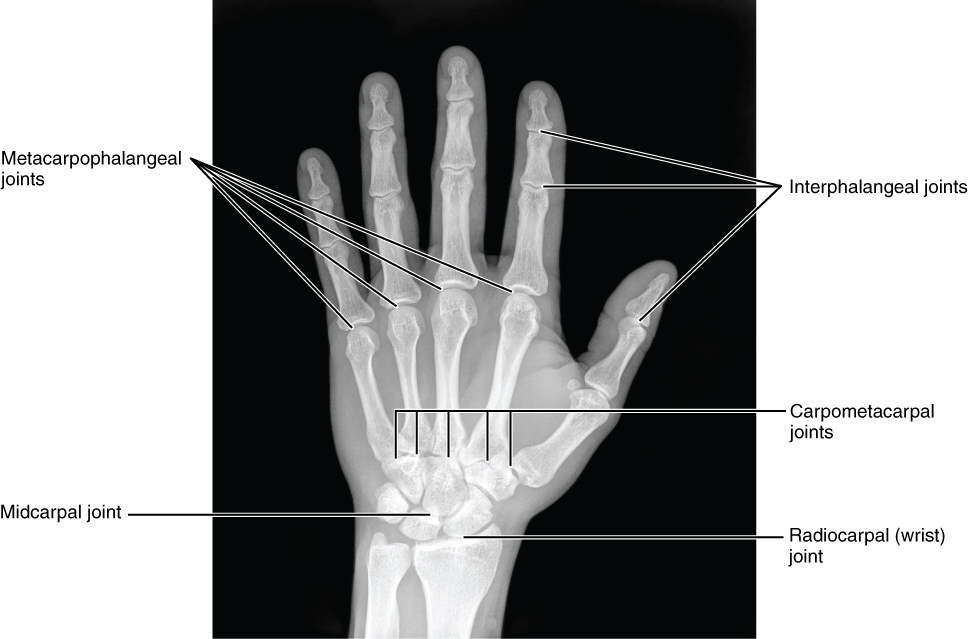

The carpal bones form the base of the hand. This can be seen in the radiograph (X-ray image) of the hand that shows the relationships of the hand bones to the skin creases of the hand (see Figure 11.2.4). Within the carpal bones, the four proximal bones are united to each other by ligaments to form a unit. Only three of these bones, the scaphoid, lunate, and triquetrum, contribute to the radiocarpal joint. The scaphoid and lunate bones articulate directly with the distal end of the radius, whereas the triquetrum bone articulates with a fibrocartilaginous pad that spans the radius and styloid process of the ulna. The distal end of the ulna thus does not directly articulate with any of the carpal bones.

The four distal carpal bones are also held together as a group by ligaments. The proximal and distal rows of carpal bones articulate with each other to form the midcarpal joint (see Figure 11.2.4). Together, the radiocarpal and midcarpal joints are responsible for all movements of the hand at the wrist. The distal carpal bones also articulate with the metacarpal bones of the hand.

Figure 11.2.4. Bones of the hand posterior view. This radiograph shows the position of the bones within the hand. Note the carpal bones that form the base of the hand. (credit: modification of work by Trace Meek).

The palm of the hand contains five elongated metacarpal bones. These bones lie between the carpal bones of the wrist and the bones of the fingers and thumb (see Figure 11.2.3). The proximal end of each metacarpal bone articulates with one of the distal carpal bones. Each of these articulations is a carpometacarpal joint (see Figure 11.2.4). The expanded distal end of each metacarpal bone articulates at the metacarpophalangeal joint with the proximal phalanx bone of the thumb or one of the fingers. The distal end also forms the knuckles of the hand, at the base of the fingers. The metacarpal bones are numbered 1–5, beginning at the thumb.

The fingers and thumb contain 14 bones, each of which is called a phalanx bone (plural = phalanges), named after the ancient Greek phalanx (a rectangular block of soldiers). The thumb (pollex) is digit number 1 and has two phalanges, a proximal phalanx, and a distal phalanx bone (see Figure 11.2.3). Digits 2 (index finger) through 5 (little finger) have three phalanges each, called the proximal, middle, and distal phalanx bones. An interphalangeal joint is one of the articulations between adjacent phalanges of the digits (see Figure 11.2.4).